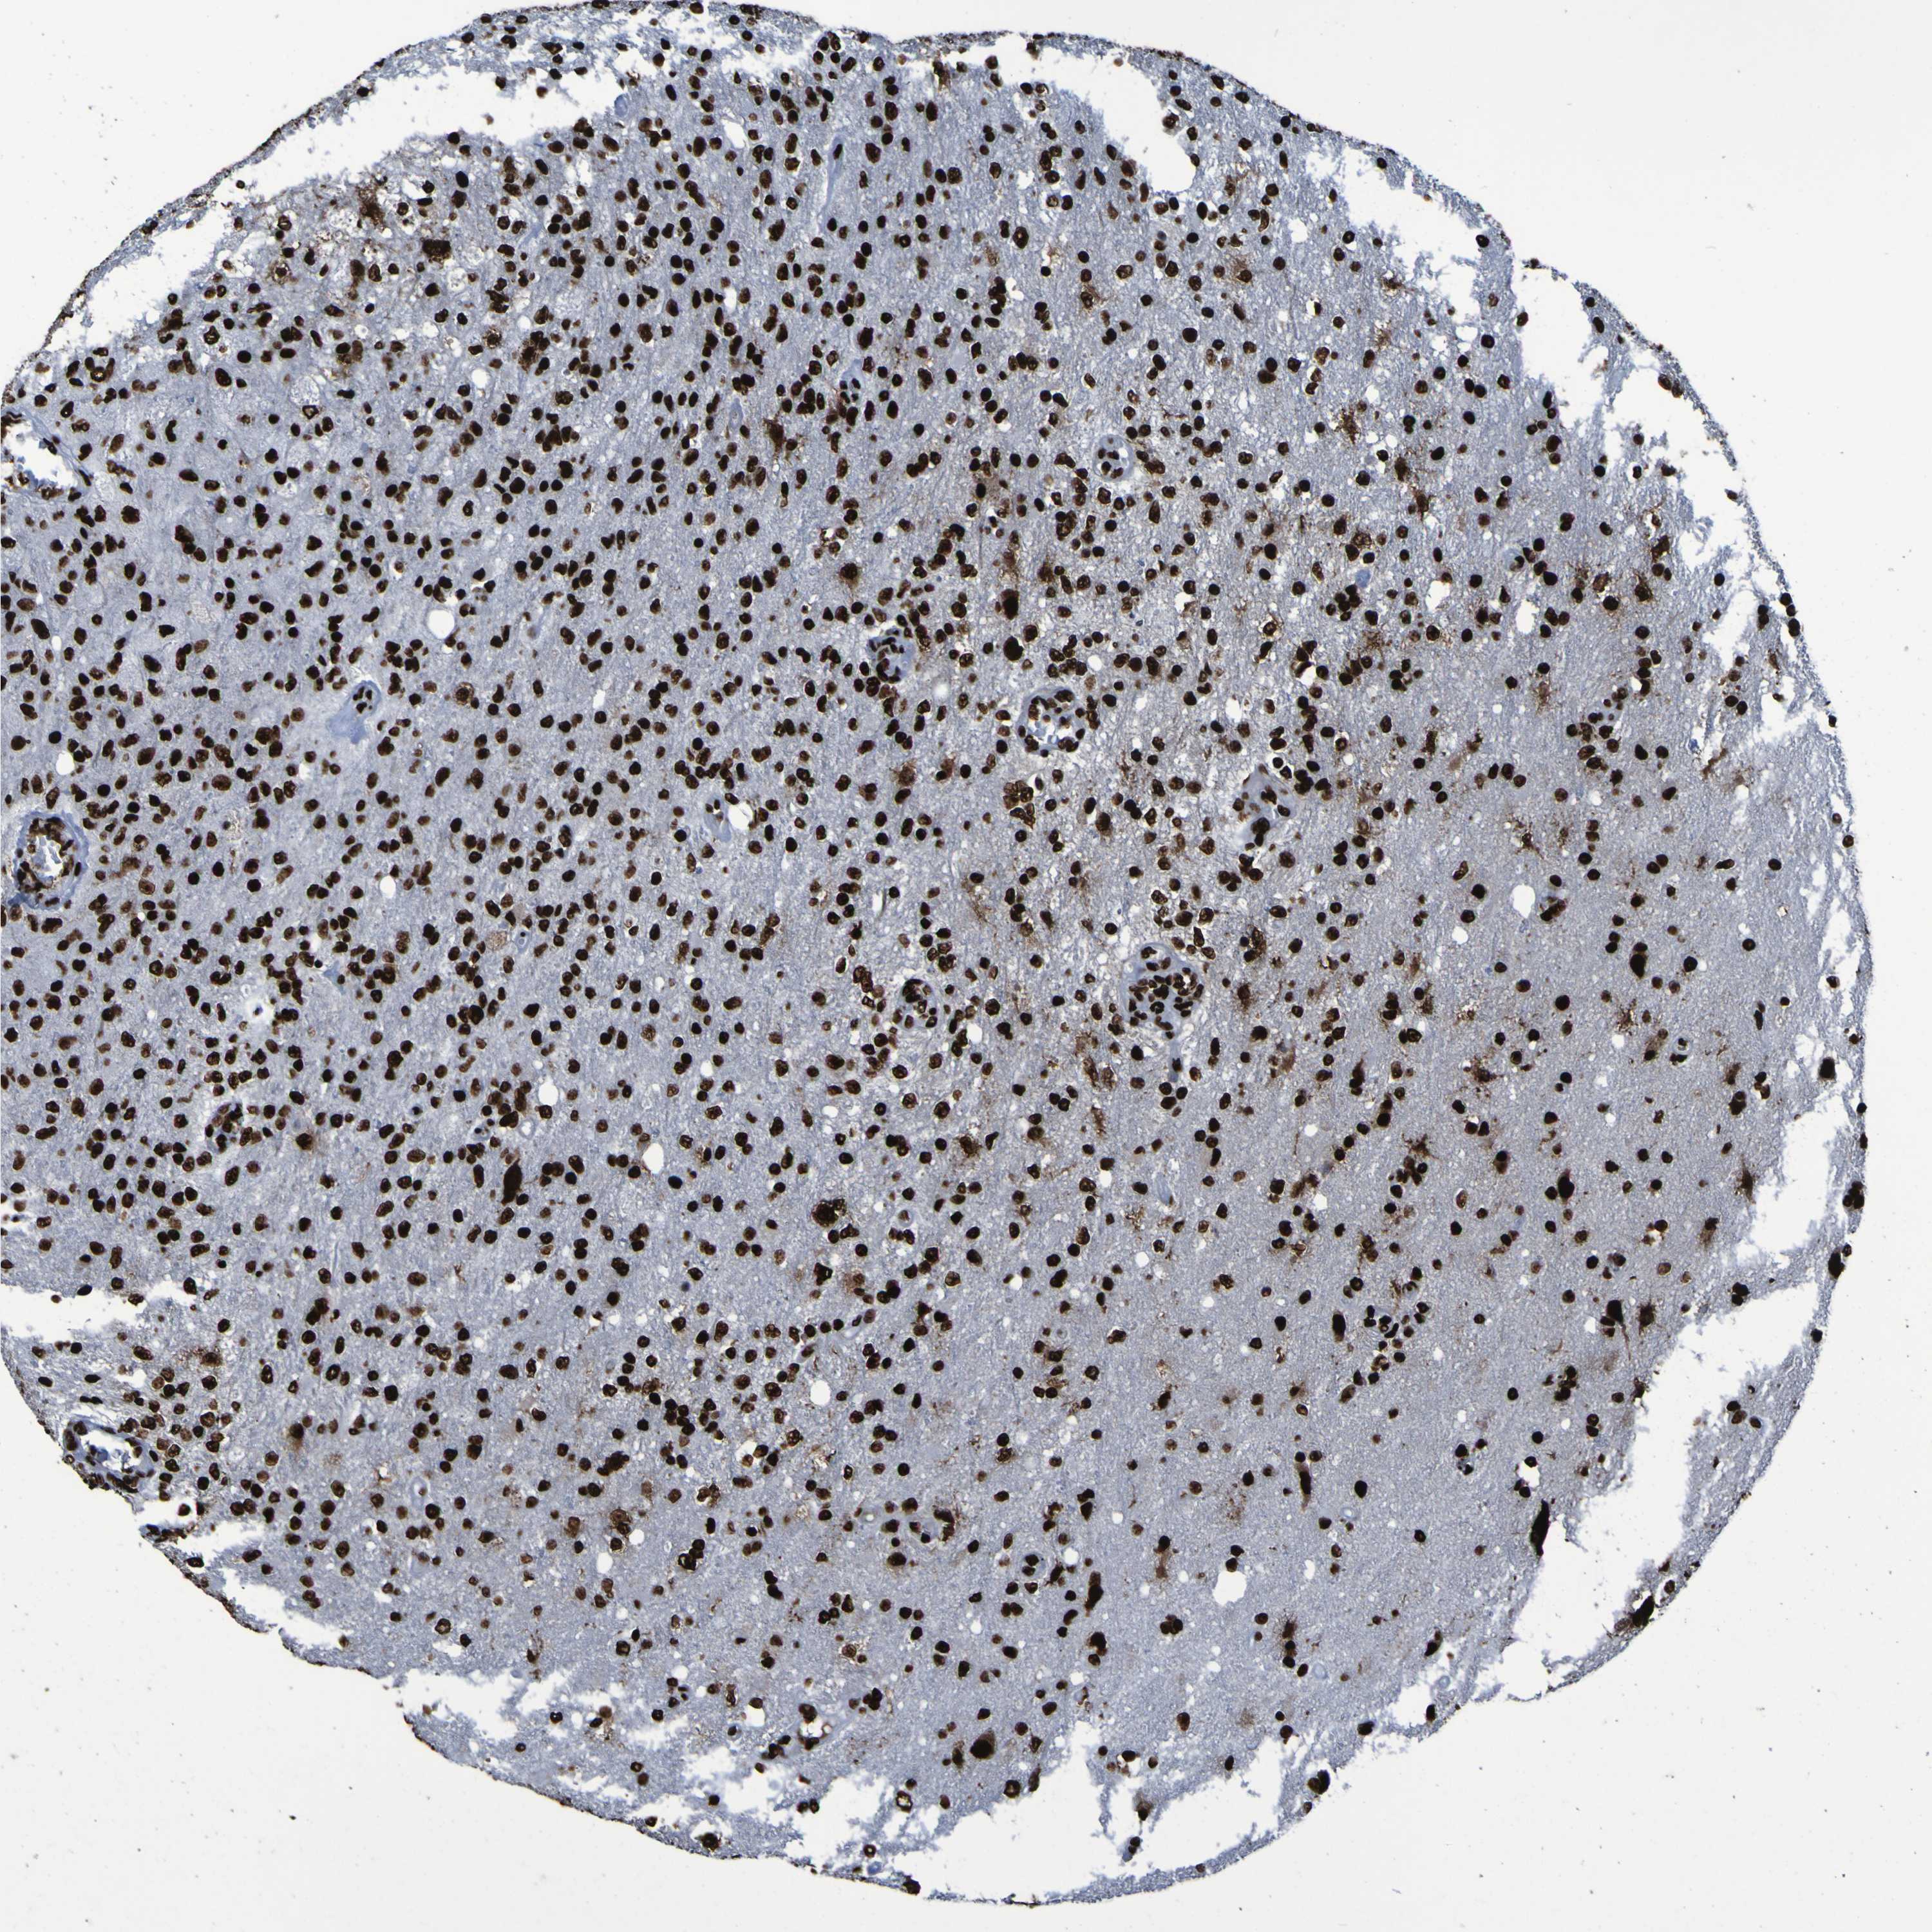

GLIOMA - Protein expressioni

A mouse-over function shows sample information and annotation data. Click on an image to view it in a full screen mode. Samples can be filtered based on level of antibody staining by selecting one or several of the following categories: high, medium, low and not detected. The assay and annotation is described here.

Note that samples used for immunohistochemistry by the Human Protein Atlas do not correspond to samples in the TCGA dataset.

Antibody stainingi

Antibody staining in the annotated cell types in the current human tissue is reported as not detected, low, medium, or high, based on conventional immunohistochemistry profiling in selected tissues. This score is based on the combination of the staining intensity and fraction of stained cells.

Each image is clickable and will lead to virtual microscopy that enables deeper exploration of all samples and also displays staining intensity scores, fraction scores and subcellular localization as well as patient and tissue information for each sample.

Antibody HPA011384

Antibody CAB012983

Staining

High

Medium

Low

Not detected

Intensity

Strong

Moderate

Weak

Negative

Quantity

>75%

75%-25%

<25%

None

Location

Nuclear

Cytoplasmic/membranous

Cytoplasmic/membranous,nuclear

Glioma, malignant, High grade

Glioma, malignant, Low grade